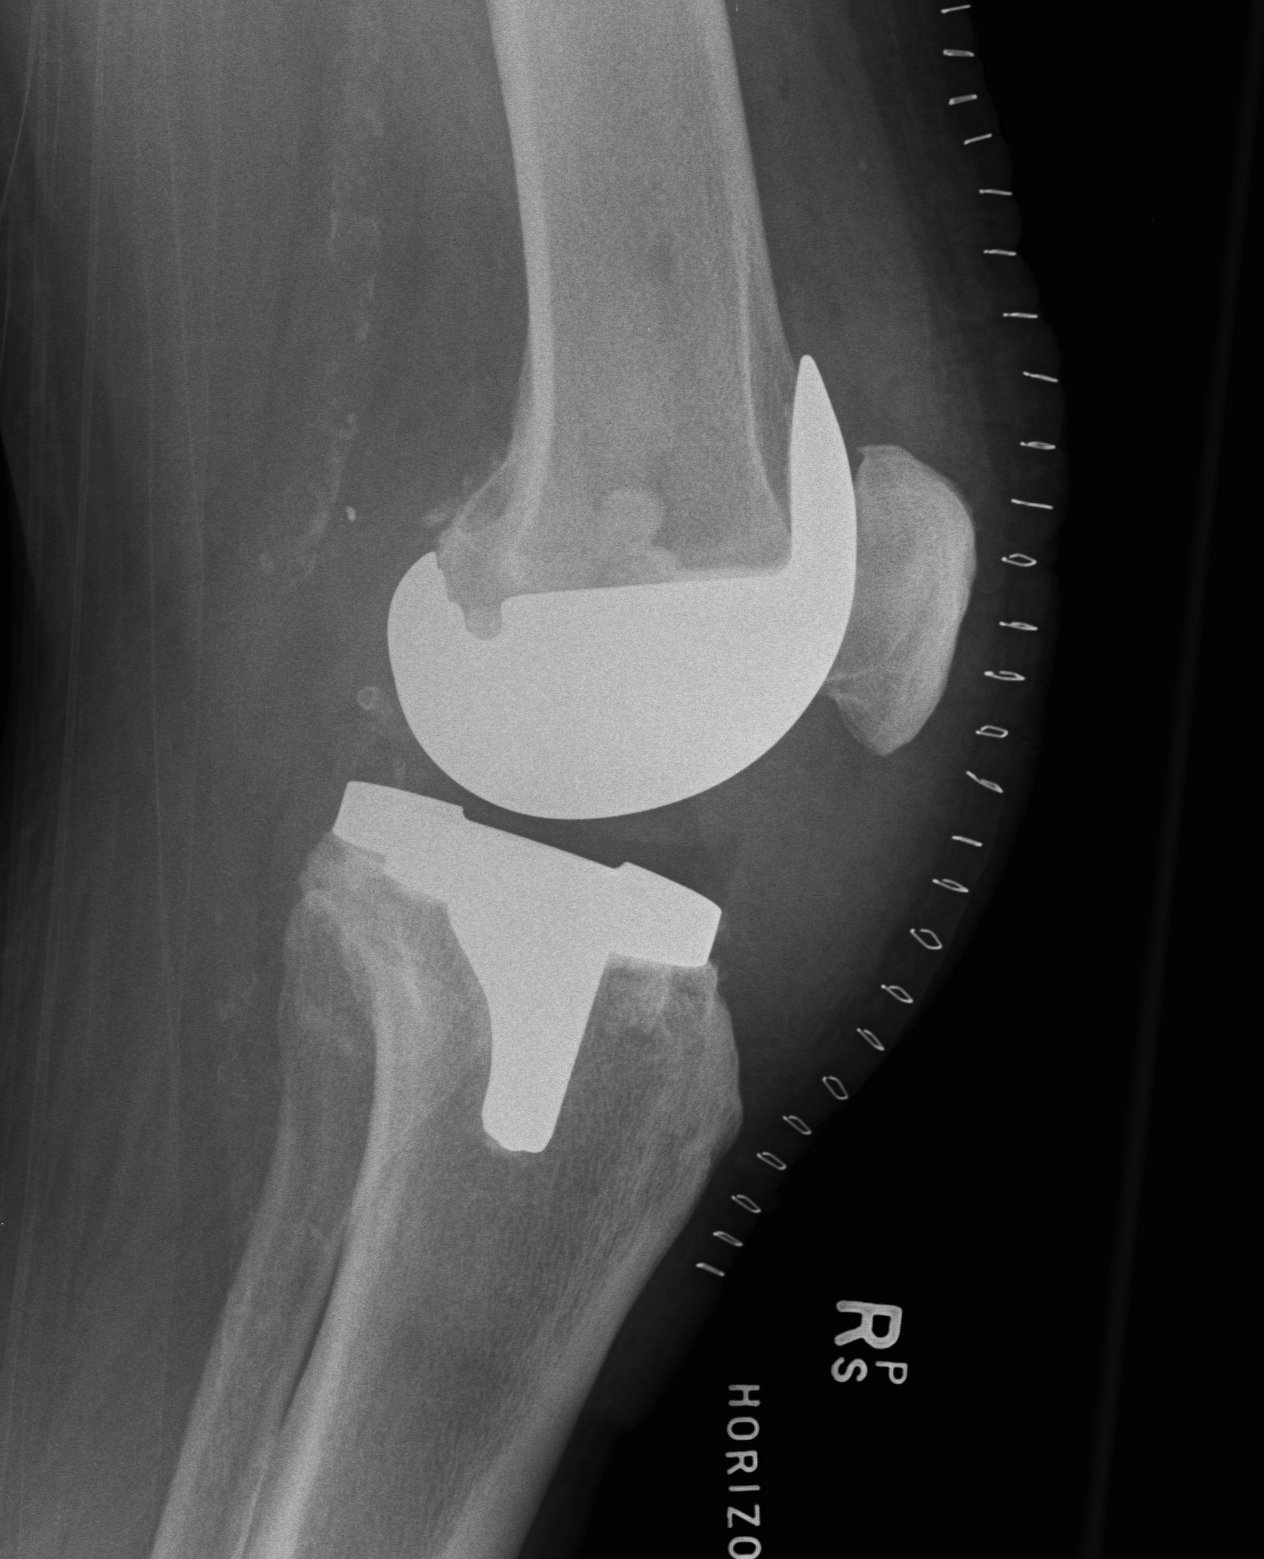

2. Constrained Non Hinged / Varus Valgus Constrained (VVC)

Design

1. Large metal reinforced post in deep femoral box

- provides greater coronal plane stability

- variable varus/valgus stability as well as rotation

- permit 2-3o of varus-valgus movement

- 2o of internal/external rotation

2. Stems

- transmit the increased stresses away from the fixation interfaces to diaphysis